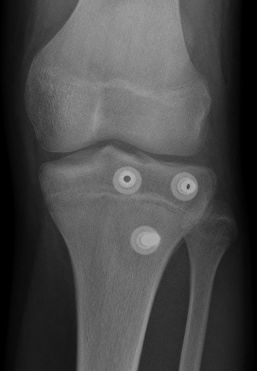

Type IB

Type IIB

Type III

Comminuted Type III